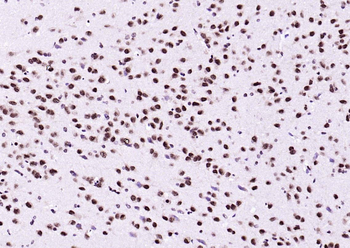

IHC staining of FFPE human brain with Ubiquitin antibody (clone PBQN-1). Required HIER: boil tissue sections in pH9 10mM Tris with 1mM EDTA for 10-20 min followed by cooling at RT for 20 min.